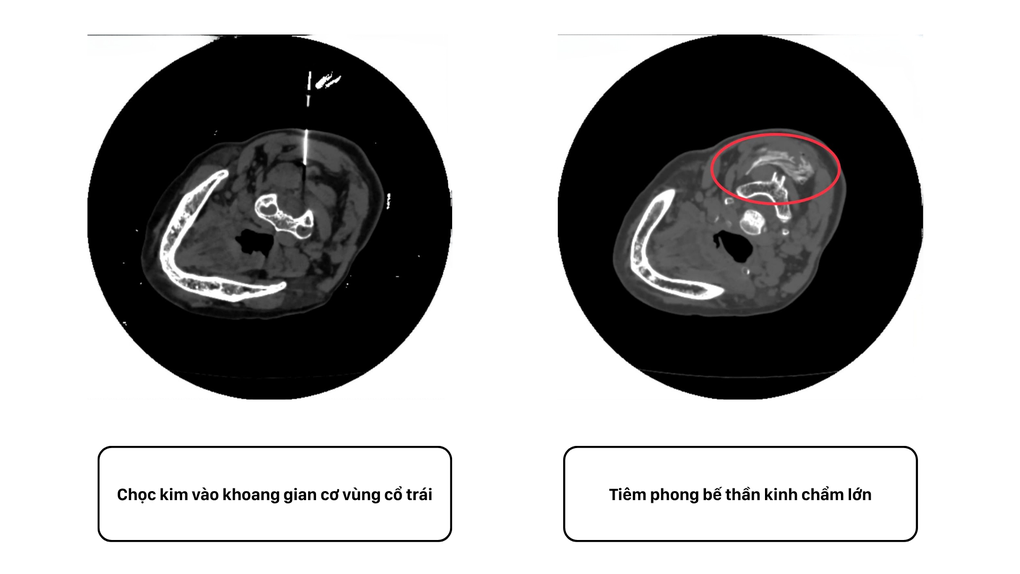

Dưới hướng dẫn của máy chụp cắt lớp vi tính hiện đại, bác sĩ đưa 1 kim nhỏ như sợi tóc có chứa hỗn hợp thuốc tê và thuốc chống viêm trực tiếp vào dây thần kinh chẩm lớn (thần kinh Arnold). Thuốc được đưa đúng vị trí đã chặn tín hiệu truyền cơn đau từ dây thần kinh tới não.

Hình ảnh đường đi của thuốc thông qua mũi kim vào dây thần kinh chẩm dưới hướng dẫn của máy chụp cắt lớp vi tính (Ảnh: BVCC).